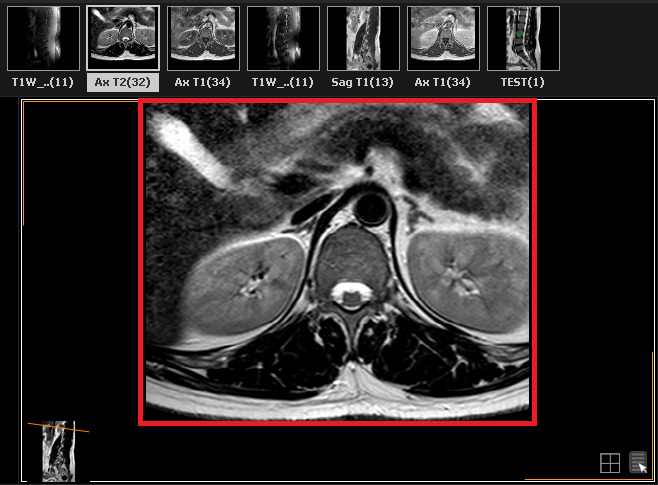

» The image window will now display the selected series: